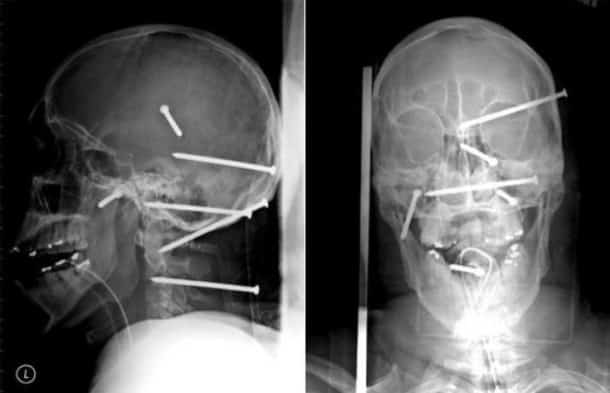

33 radiographies qui prouvent que les gens font des choses douteuses avec leur corps !